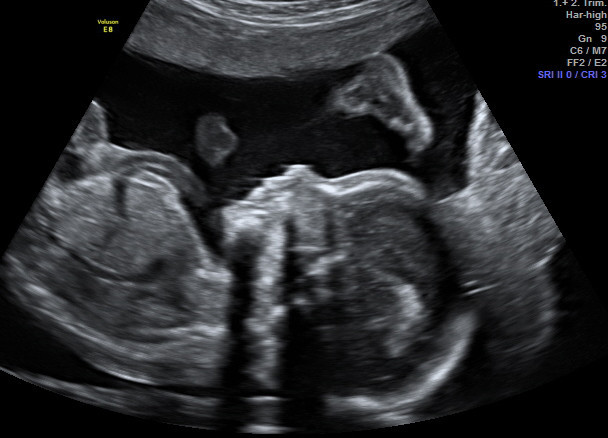

Pränataldiagnostik

• Ersttrimesterscreening - Nackentranzparenz (NT)-Messung mit Risikoberechnung für Trisomie 21, 13 und 18 in Verbindung mit früher Feindiagnostik zwischen 11+0 und 14+0 Schwangerschaftswochen

• Feindiagnostik - Organultraschall 19.-22 SSW